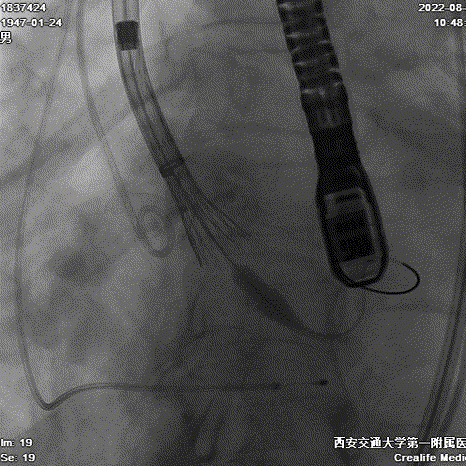

Evolut PRO 的递送系统对入路要求小,顺应性出色,装载瓣膜后仍能良好地顺应工作导丝形态,有效避免了对该患者降主动脉水肿部位的压迫,轻松抵达释放位置。

递送到达释放位

Type0型二叶瓣伴偏心性钙化导致瓣膜定位困难,如果释放位置偏浅,瓣膜蹦出风险高。术者利用Evolut PRO稳定的多次可回收功能,通过调整瓣膜植入深度,确保瓣膜流入端稳固锚定在瓣环根部。通过造影评估,瓣膜植入位置理想,因此进行过最后缓慢释放,瓣膜顺利达到目标植入深度。